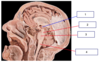

Correctly label 1-4 from the picture

- Dura matter (outer and inner)

- Arachnoid

- Subarachnoid space

- Pia Matter